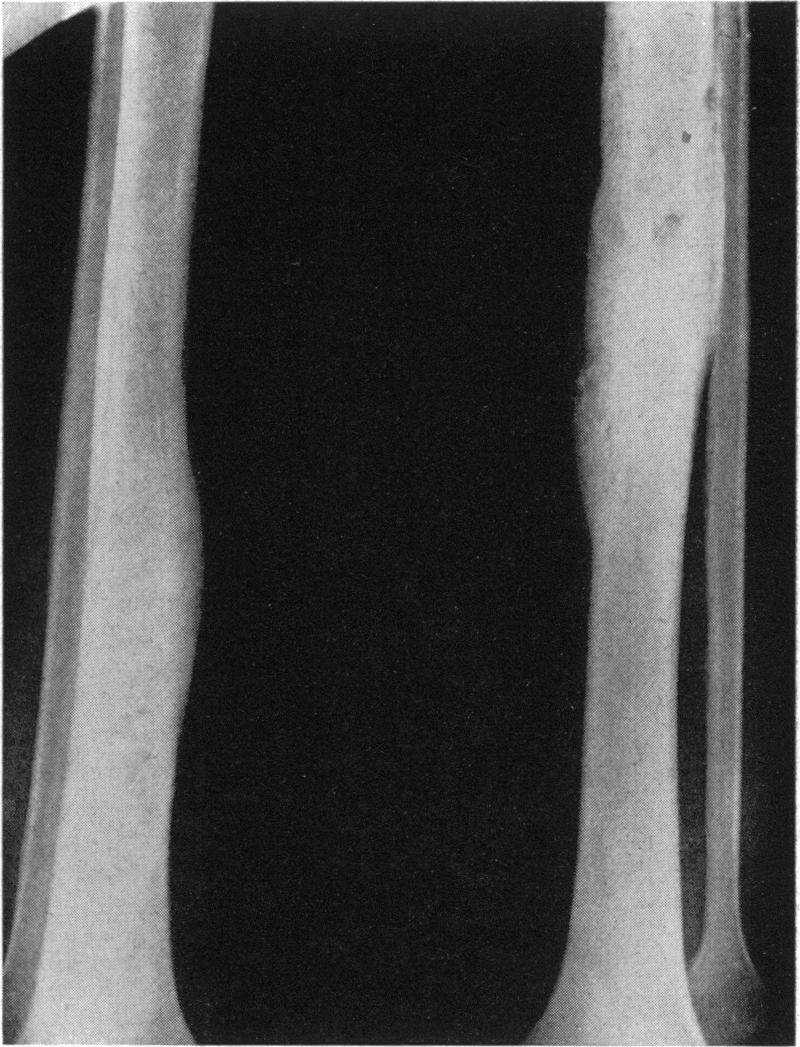

A form of endemic syphilis exists in the Bakwena Reserve of the Bechuanaland Protectorate known by the local name of "dichuchwa". It is similar to bejel, njovera and the endemic syphilis reported elsewhere in the world. The Government of the Protectorate, with the assistance of WHO and UNICEF, began in November 1953 a mass campaign in the Reserve to control this disease and, at the same time, to study its epidemiological, clinical, social and therapeutic aspects. The seropositivity rate in the Reserve was found to be 37%.Dichuchwa is a childhood and family disease, usually spread non-venereally. The early lesions are similar to secondary lesions of sporadic venereal syphilis, and are often followed by tertiary lesions affecting mainly the skin, nasopharynx and long bones. Primary lesions are rare but may occur under certain epidemiological conditions if the inoculum is sufficiently large; thus a mother may develop primary sores on the nipples through suckling an infected infant. Lesions of the cardiovascular and central nervous systems and congenital syphilis are also rare. Superinfection of an already infected and allergic host is probably the chief reason for the frequency of the tertiary lesions.Treatment of the disease with penicillin is very effective, and the authors believe that mass treatment of cases and contacts combined with an improvement in the standards of hygiene could eradicate the disease.

在贝专纳兰保护地的巴克韦纳保护区存在一种地方性梅毒,当地称之为“迪楚瓦病”。它与非性病性梅毒、恩乔韦拉病以及世界其他地方报道的地方性梅毒相似。在世界卫生组织和联合国儿童基金会的协助下,保护地政府于1953年11月在该保护区发起了一场大规模防治这种疾病的运动,同时研究其流行病学、临床、社会和治疗方面的情况。发现该保护区的血清阳性率为37%。迪楚瓦病是一种儿童和家庭疾病,通常通过非性途径传播。早期损害类似于散发性性病梅毒的二期损害,随后常出现三期损害,主要影响皮肤、鼻咽和长骨。一期损害很少见,但在某些流行病学条件下,如果接种量足够大,也可能发生;例如,母亲在哺乳感染婴儿时,乳头可能出现一期溃疡。心血管和中枢神经系统损害以及先天性梅毒也很少见。已经感染且过敏的宿主发生重复感染可能是三期损害常见的主要原因。用青霉素治疗这种疾病非常有效,作者认为对病例和接触者进行大规模治疗并提高卫生标准可以根除这种疾病。